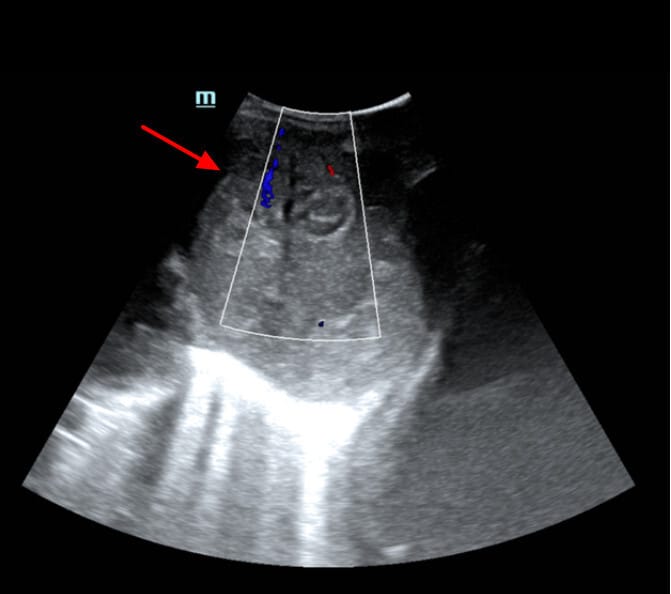

초음파 영상 소견

초음파에서 간세포암(Hepatocellular Carcinoma)은 결절형, 괴상형, 미만형으로 분류됩니다. 이 세 가지 형태는 육안적 병리 형태와도 밀접한 관련이 있습니다.

| 결절형(Nodular type) |

| – 가장 흔한 형태이며, 단일 또는 다발성 결절로 관찰됨 |

| – 경계가 비교적 명확하고 둥근 형태 |

| – 저에코(hypoechoic), 혼합에코(mixed echo), 혹은 고에코(hyperechoic)로 보일 수 있음 |

| – 크기가 커질수록 내부 괴사, 석회화, 출혈 등으로 이질적인 음영을 보임 |

ElBeialy M, Hepatocellular carcinoma with metastatic porta-hepatis lymphadenopathy and IHBR dilatation. Case study, Radiopaedia.org (Accessed on 21 Apr 2025) https://doi.org/10.53347/rID-35511

초음파 소견상 특징

- Right liver lobe segment V well-defined hypoechoic lesion